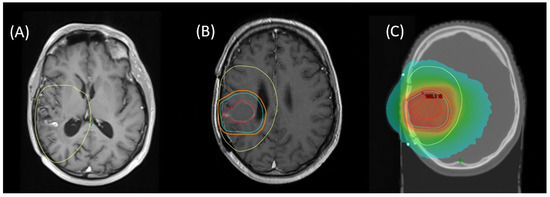

Re-RT planning was performed in accordance with ICRU8325. All patients were treated with 1.8–2 Gy daily fractions 5/week with IMRT-planning for conformal treatment volumes. All treatment plans and target volume definitions of patients included in this cohort were assessed. Treatment planning for all patients was realized via Varian Eclipse (by Varian medical systems, Palo Alto, CA, USA) or TomoTherapy® (by Accuray Inc., Sunnyvale, CA, USA). Diagnostic MRI was co-registered with the planning CT for all patients. Patients were treated with immobilization by a thermoplastic mask, using 6 MV or 15 MV Photons in different beam setups (Intensity Modulated Radiation Therapy [IMRT] or Volumetric Intensity Modulated Arc Therapy [VMAT], with helical therapy as a special form of VMAT). Re-RT target volumes were defined as standardized by ICRU50 with the gross tumor volume (GTV) enclosing the primary disease site (defined as sites of recurrent or progressing tumor after initial treatment, marked by blood–brain barrier disruptions in contrast-enhanced T1- and T2-MRI), the clinical target volume (CTV) incorporating sites of suspected subclinical infiltration (also considering the T2-FLAIR-signal if clinically appropriate), and the planning target volume (PTV) creating an additional margin to compensate for possible incongruences in patient positioning (usually 3–5 mm). For patients who received prior re-resection, the CTV was defined as areas of supposed residual tumor or associated with a high risk of subclinical infiltration, based on postoperative MRI (T2 and contrast-enhanced T1) with an additional margin, based on disease location and size, prior treatment, extent of resection, and clinical performance status. Postoperative patients with delayed initiation of radiation treatment (>3 weeks) received a dedicated planning MRI. An example for target volume definition and dose distribution is given in Figure 1.

Figure 1. Example for (A) MRI of recurrent blood–brain barrier disruption of the right temporal lobe as a manifestation of recurrent glioblastoma, fused with initial RT planning CT to show first-line treatment PTV (yellow). (B) Planning MRI after surgical resection for fusion with planning CT with resulting target volumes for re-RT (GTV = red, CTV = cyan, PTV = orange). (C) Resulting cumulative dose distribution for re-irradiation with 39.6 Gy via helical therapy.